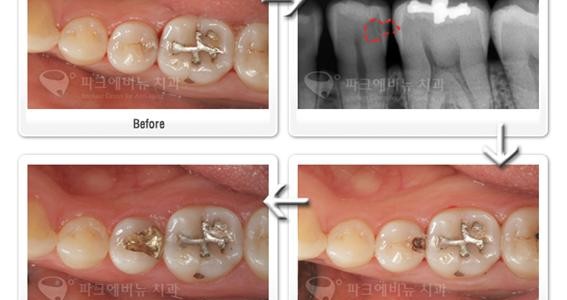

기존 아말감 부위가 너무 넓거나 옆면까지 연결이 되어있는 경우에는 아래 사진처럼 금으로 때우는 것이 깨질 위험도 줄어들고 좀 더 튼튼하게 사용할 수 있습니다.

아말감 교체치료 금 인레이의 장점

- 아말감교체 후, 깨질 위험이 없다.

- 비교적 넓은 부위의 충치에도 인레이를 적용할 수 있다.

때워야 할 부위가 크다고 해서 꼭 하얀색 나는 재료로 아말감교체 치료를 못하는 것은 아닙니다. 하얀색 나는 재료의 종류에는 레진 인레이, 세라믹 인레이 등이 있고 때워야 할 부위가 좀 크다면, 레진 인레이 보다는 강도가 더 좋은 세라믹 인레이를 사용하면 됩니다. 다만, 세라믹 인레이의 범위를 넘어선 경우에는 치아의 보호를 위해서라도 금 인레이나, 크라운 치료를 받으실 것을 권유 드립니다.

크라운치료는 치아를 전체적으로 삭제하여 씌워주는 아말감교체 치료입니다. 충치나 기존충전물 부위가 넓어 인레이가 힘들 경우에 적용되며, 탈락 위험이나 깨질 위험이 인레이에 비해 현저히 줄어듭니다.